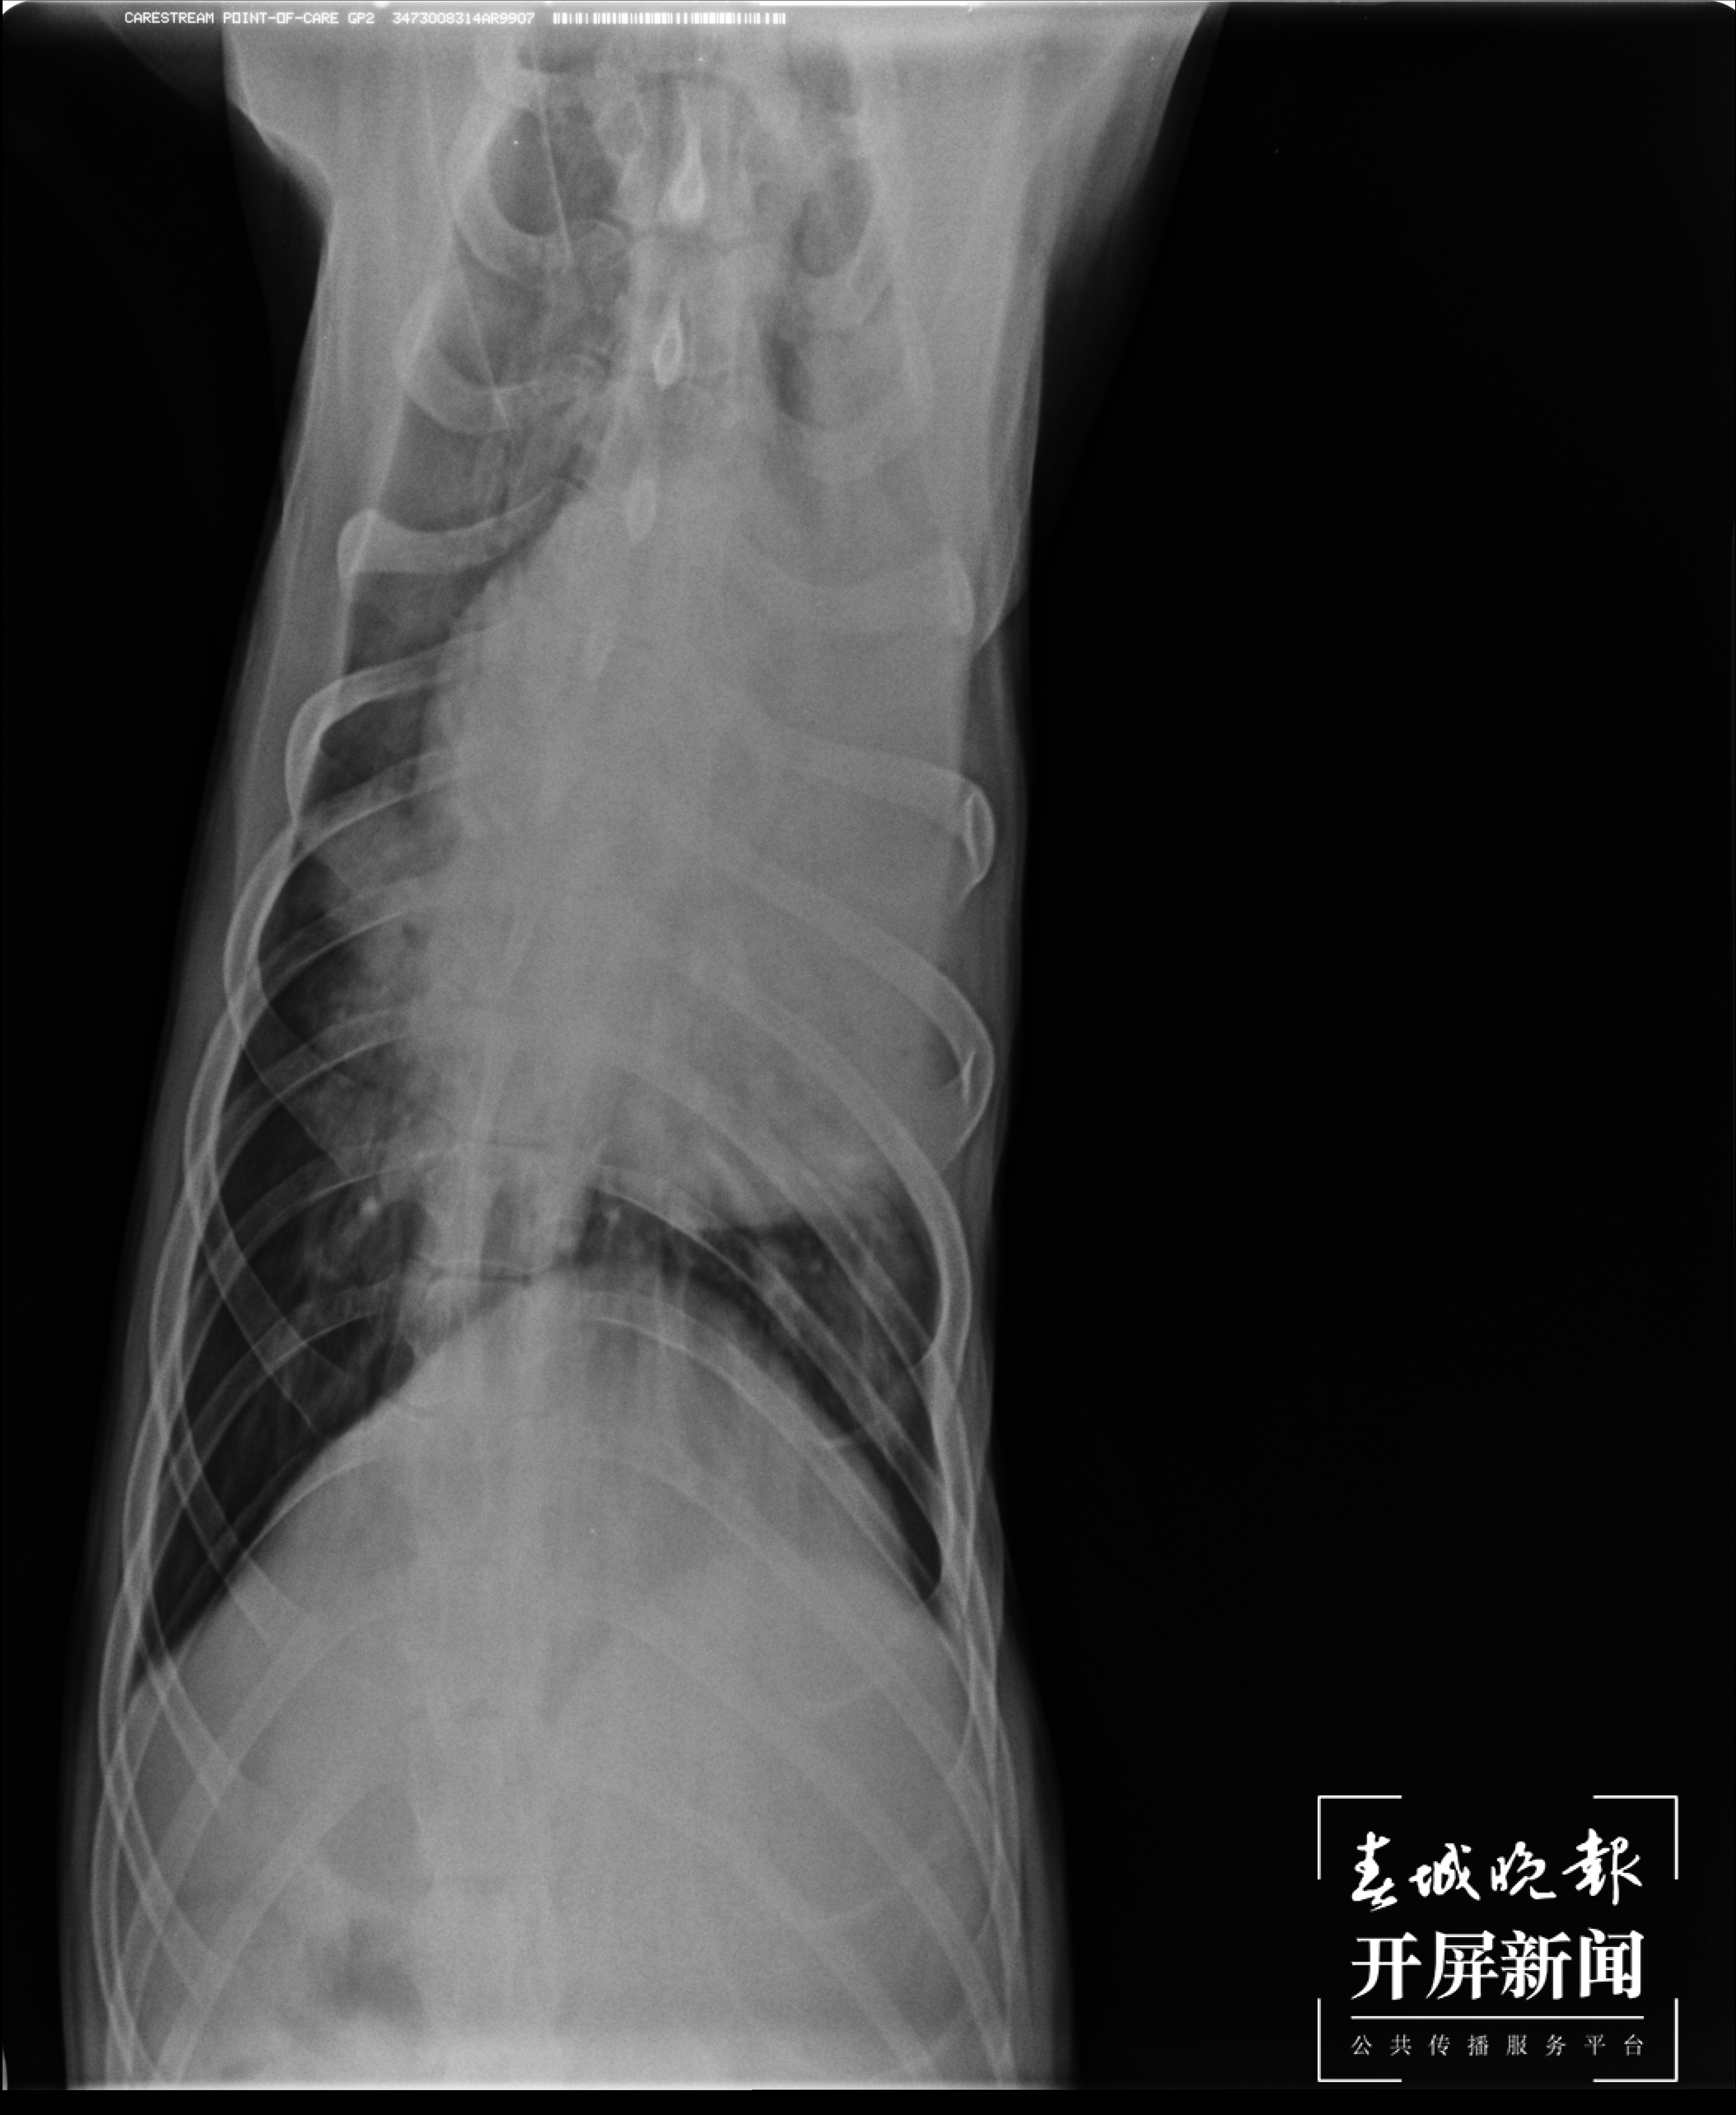

▲2月19日,CT显示肺部水肿严重。(受访者供图)